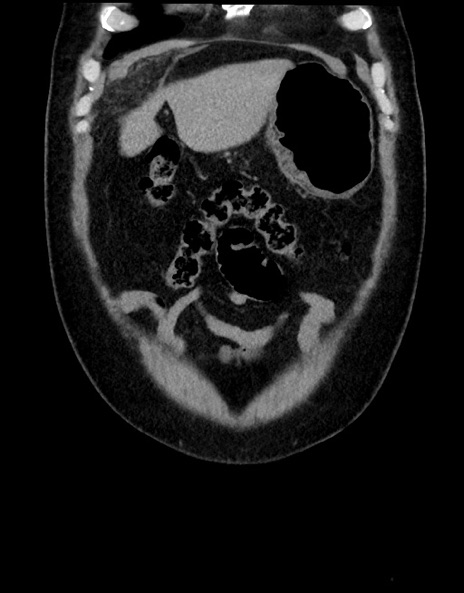

症例15(冠状断像)

横断像